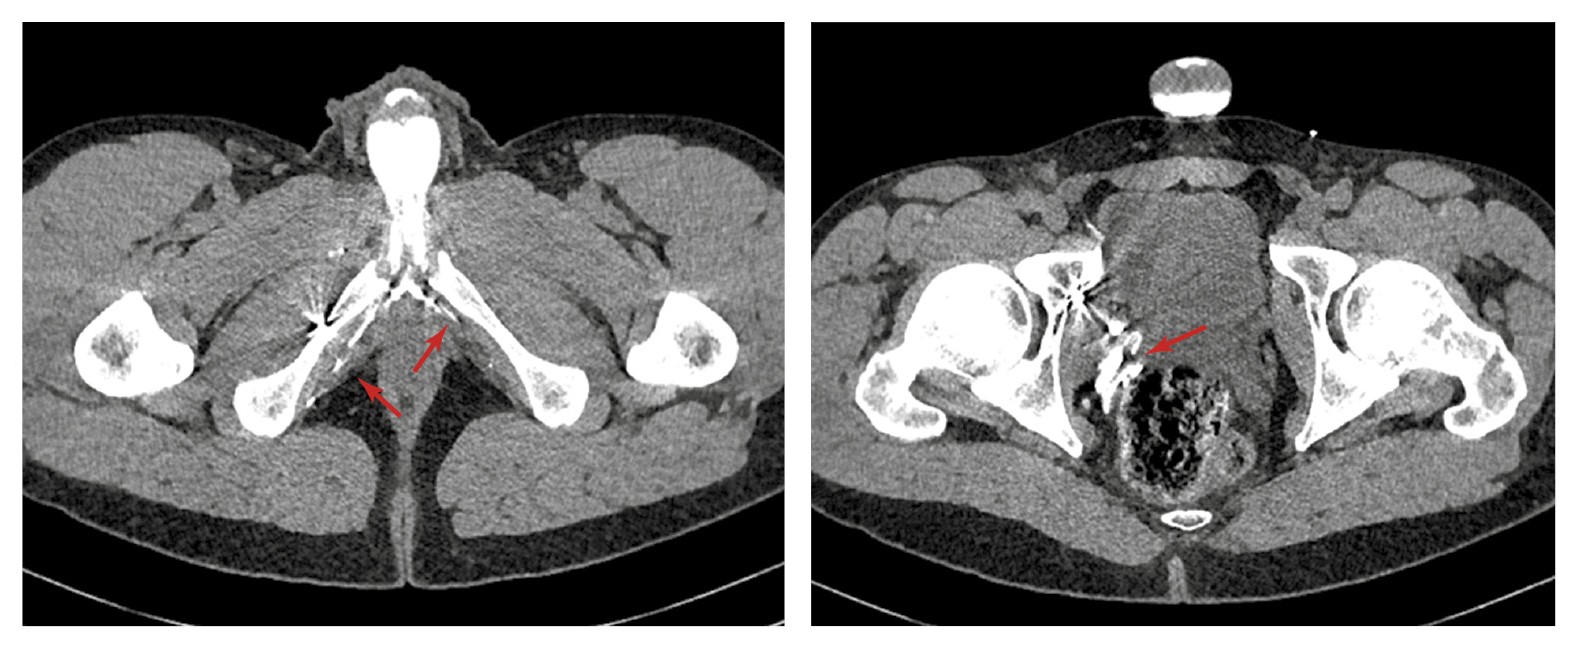

С целью подтверждения венозной утечки и оценки венозной анатомии половой системы пациенту проведена МСКТ-кавернозография. Фармакологическую стимуляцию осуществляли посредством введения 10 мкг простагландина интракавернозно. Получены изображения в нативную фазу (до введения контрастного вещества), а также через 30 с, 1, 3 и 5 мин после интракавернозного введения контрастного препарата (йогексола 350 мг/мл, 50 мл). По данным КТ в области наружной и внутренней поверхностей правой лобковой кости определяются множественные гиперденсивные структуры, вероятно, эмболизационные спирали (рис. 2).

Рис. 2. Данные МСТК-кавернозографии больного К. Стрелкой указаны гиперденсивные инородные структуры (вероятно, спирали) в области правой лобковой кости.

В левой общей подвздошной вене с выходом в нижнюю полую вену определяется стент (рис. 3).

Рис. 3. Данные МСТК-кавернозографии больного К. Стрелкой указан стент в левой общей подвздошной вене.